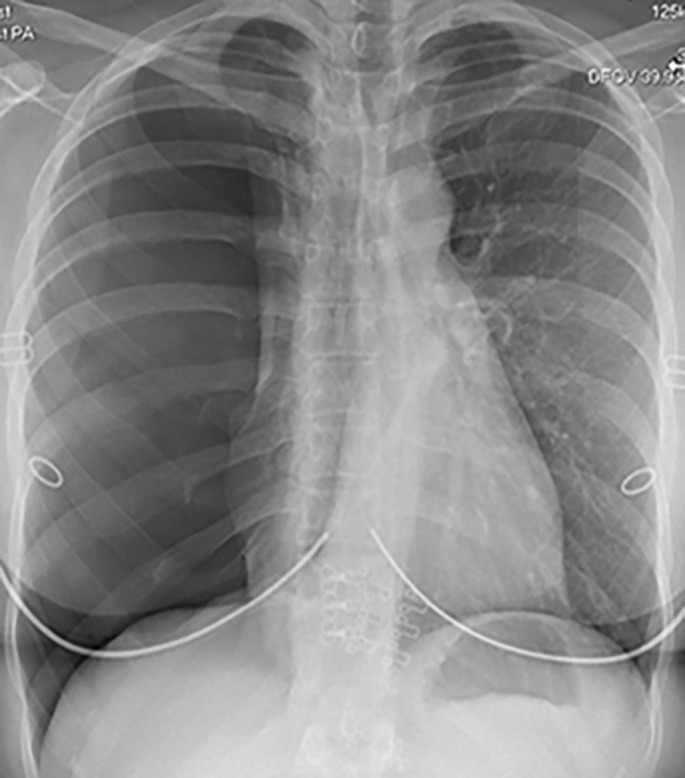

One of the respiratory complications of rheumatoid arthritis (RA) is formation of lung nodules, which can rupture to cause pneumothoraces. We present a case of recurrent pneumothoraces due to accelerated RA nodulosis, secondary to biologic therapy. https://bit.ly/3WBhgOe.

Abstract Image